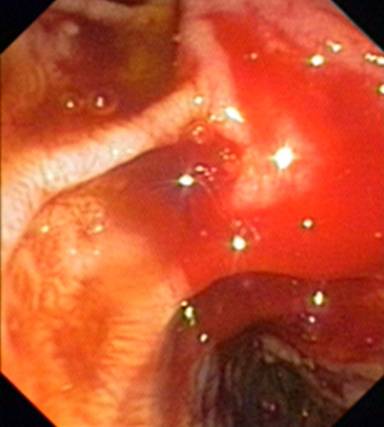

Investigations revealed hemoglobin of 4.5 g/dL (reference range: 11.0-15.0 g/dL), total lymphocyte count 12x103 mm-3 (reference range: 4-10 x103 mm-3), platelets 180 x103 mm-3 (reference range: 150-450 x103 mm-3), INR 1.2, serum creatinine 1.1 g/dL (reference range: 0-6-1.3 g/dL), serum bilirubin 0.8 mg/dL (reference range: 0.2-1.0 mg/dL), AST 42 IU/mL (reference range: 0-42 IU/mL), ALT 32 IU/mL (reference range: 0-60 IU/mL), serum alkaline phosphate 126 IU/L (reference range: 39-117 IU/mL). An ultrasound examination of the abdomen revealed mildly coarse echo-texture of liver, with portal vein diameter of 13 mm, and mild periportal collaterals. Intrahepatic bile ducts were normal; the common bile duct was of 8 mm and gallbladder and spleen were normal. Pancreatic head was bulky and heterogeneously hypoechoic while body and tail of the pancreas were normal. Upper gastrointestinal endoscopy revealed an ulcer in the medial wall of the second part of the duodenum with fresh oozing of blood (Figure 1). The oozing was controlled by injection of 10 mL of 1:10,000 adrenaline at the base of the ulcer. Serum amylase was found to be 462 IU/mL (reference range: 5-100 IU/mL), suggestive of pancreatitis.

Figure 2. Endoscopic image of the bleed from the medial wall of the second part of duodenum. |